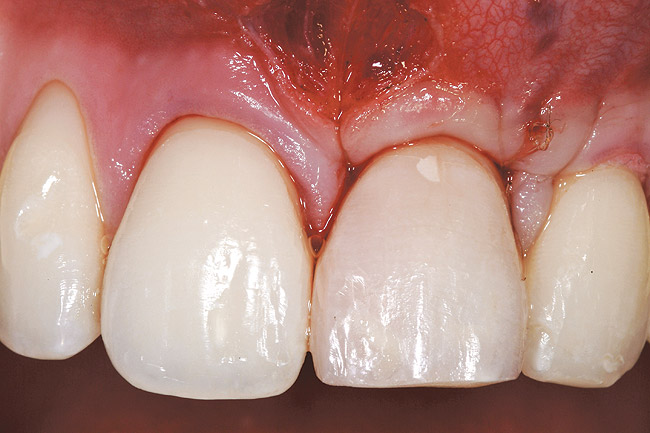

Figure 2  Case One Pretreatment clinical view, Case 1, maxillary anterior.

Figure 2

A 54-year-old non-smoking woman presented for correction of deep-wide gingival recession in the maxillary anterior (Figure 1 through Figure 3). The patient’s desires were to correct the gingival recession, balance the heights of contour of the tissues, and possibly undergo esthetic enhancement of the maxillary anterior with veneer restorations.

The 2.5-week postoperative clinical view can be seen in Figure 10 through Figure 12. Note the rapid soft tissue healing and maturation. At 6-weeks postoperative, tissue plasty was accomplished to blend the thickened keratinized tissue, in addition to placement of class V composite restorations at teeth Nos. 5, 6, and 11 to create a new restorative margin on the root surfaces.